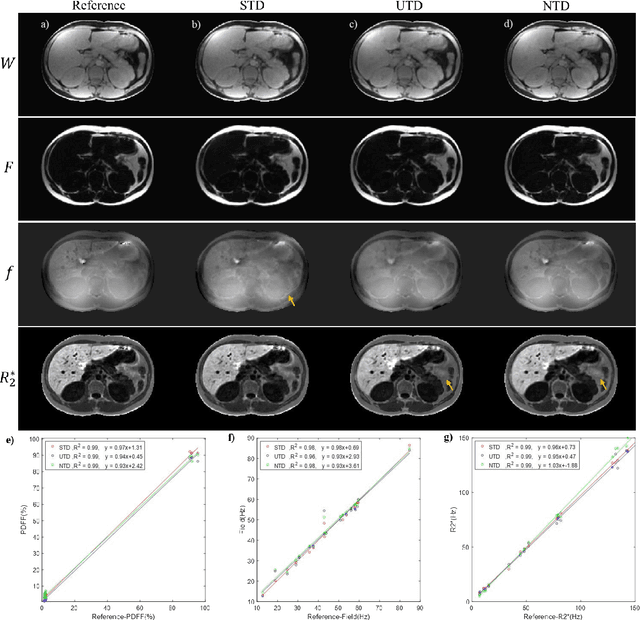

Abstract:Purpose: To use a deep neural network (DNN) for solving the optimization problem of water/fat separation and to compare supervised and unsupervised training. Methods: The current T2*-IDEAL algorithm for solving fat/water separation is dependent on initialization. Recently, deep neural networks (DNN) have been proposed to solve fat/water separation without the need for suitable initialization. However, this approach requires supervised training of DNN (STD) using the reference fat/water separation images. Here we propose two novel DNN water/fat separation methods 1) unsupervised training of DNN (UTD) using the physical forward problem as the cost function during training, and 2) no-training of DNN (NTD) using physical cost and backpropagation to directly reconstruct a single dataset. The STD, UTD and NTD methods were compared with the reference T2*-IDEAL. Results: All DNN methods generated consistent water/fat separation results that agreed well with T2*-IDEAL under proper initialization. Conclusion: The water/fat separation problem can be solved using unsupervised deep neural networks.